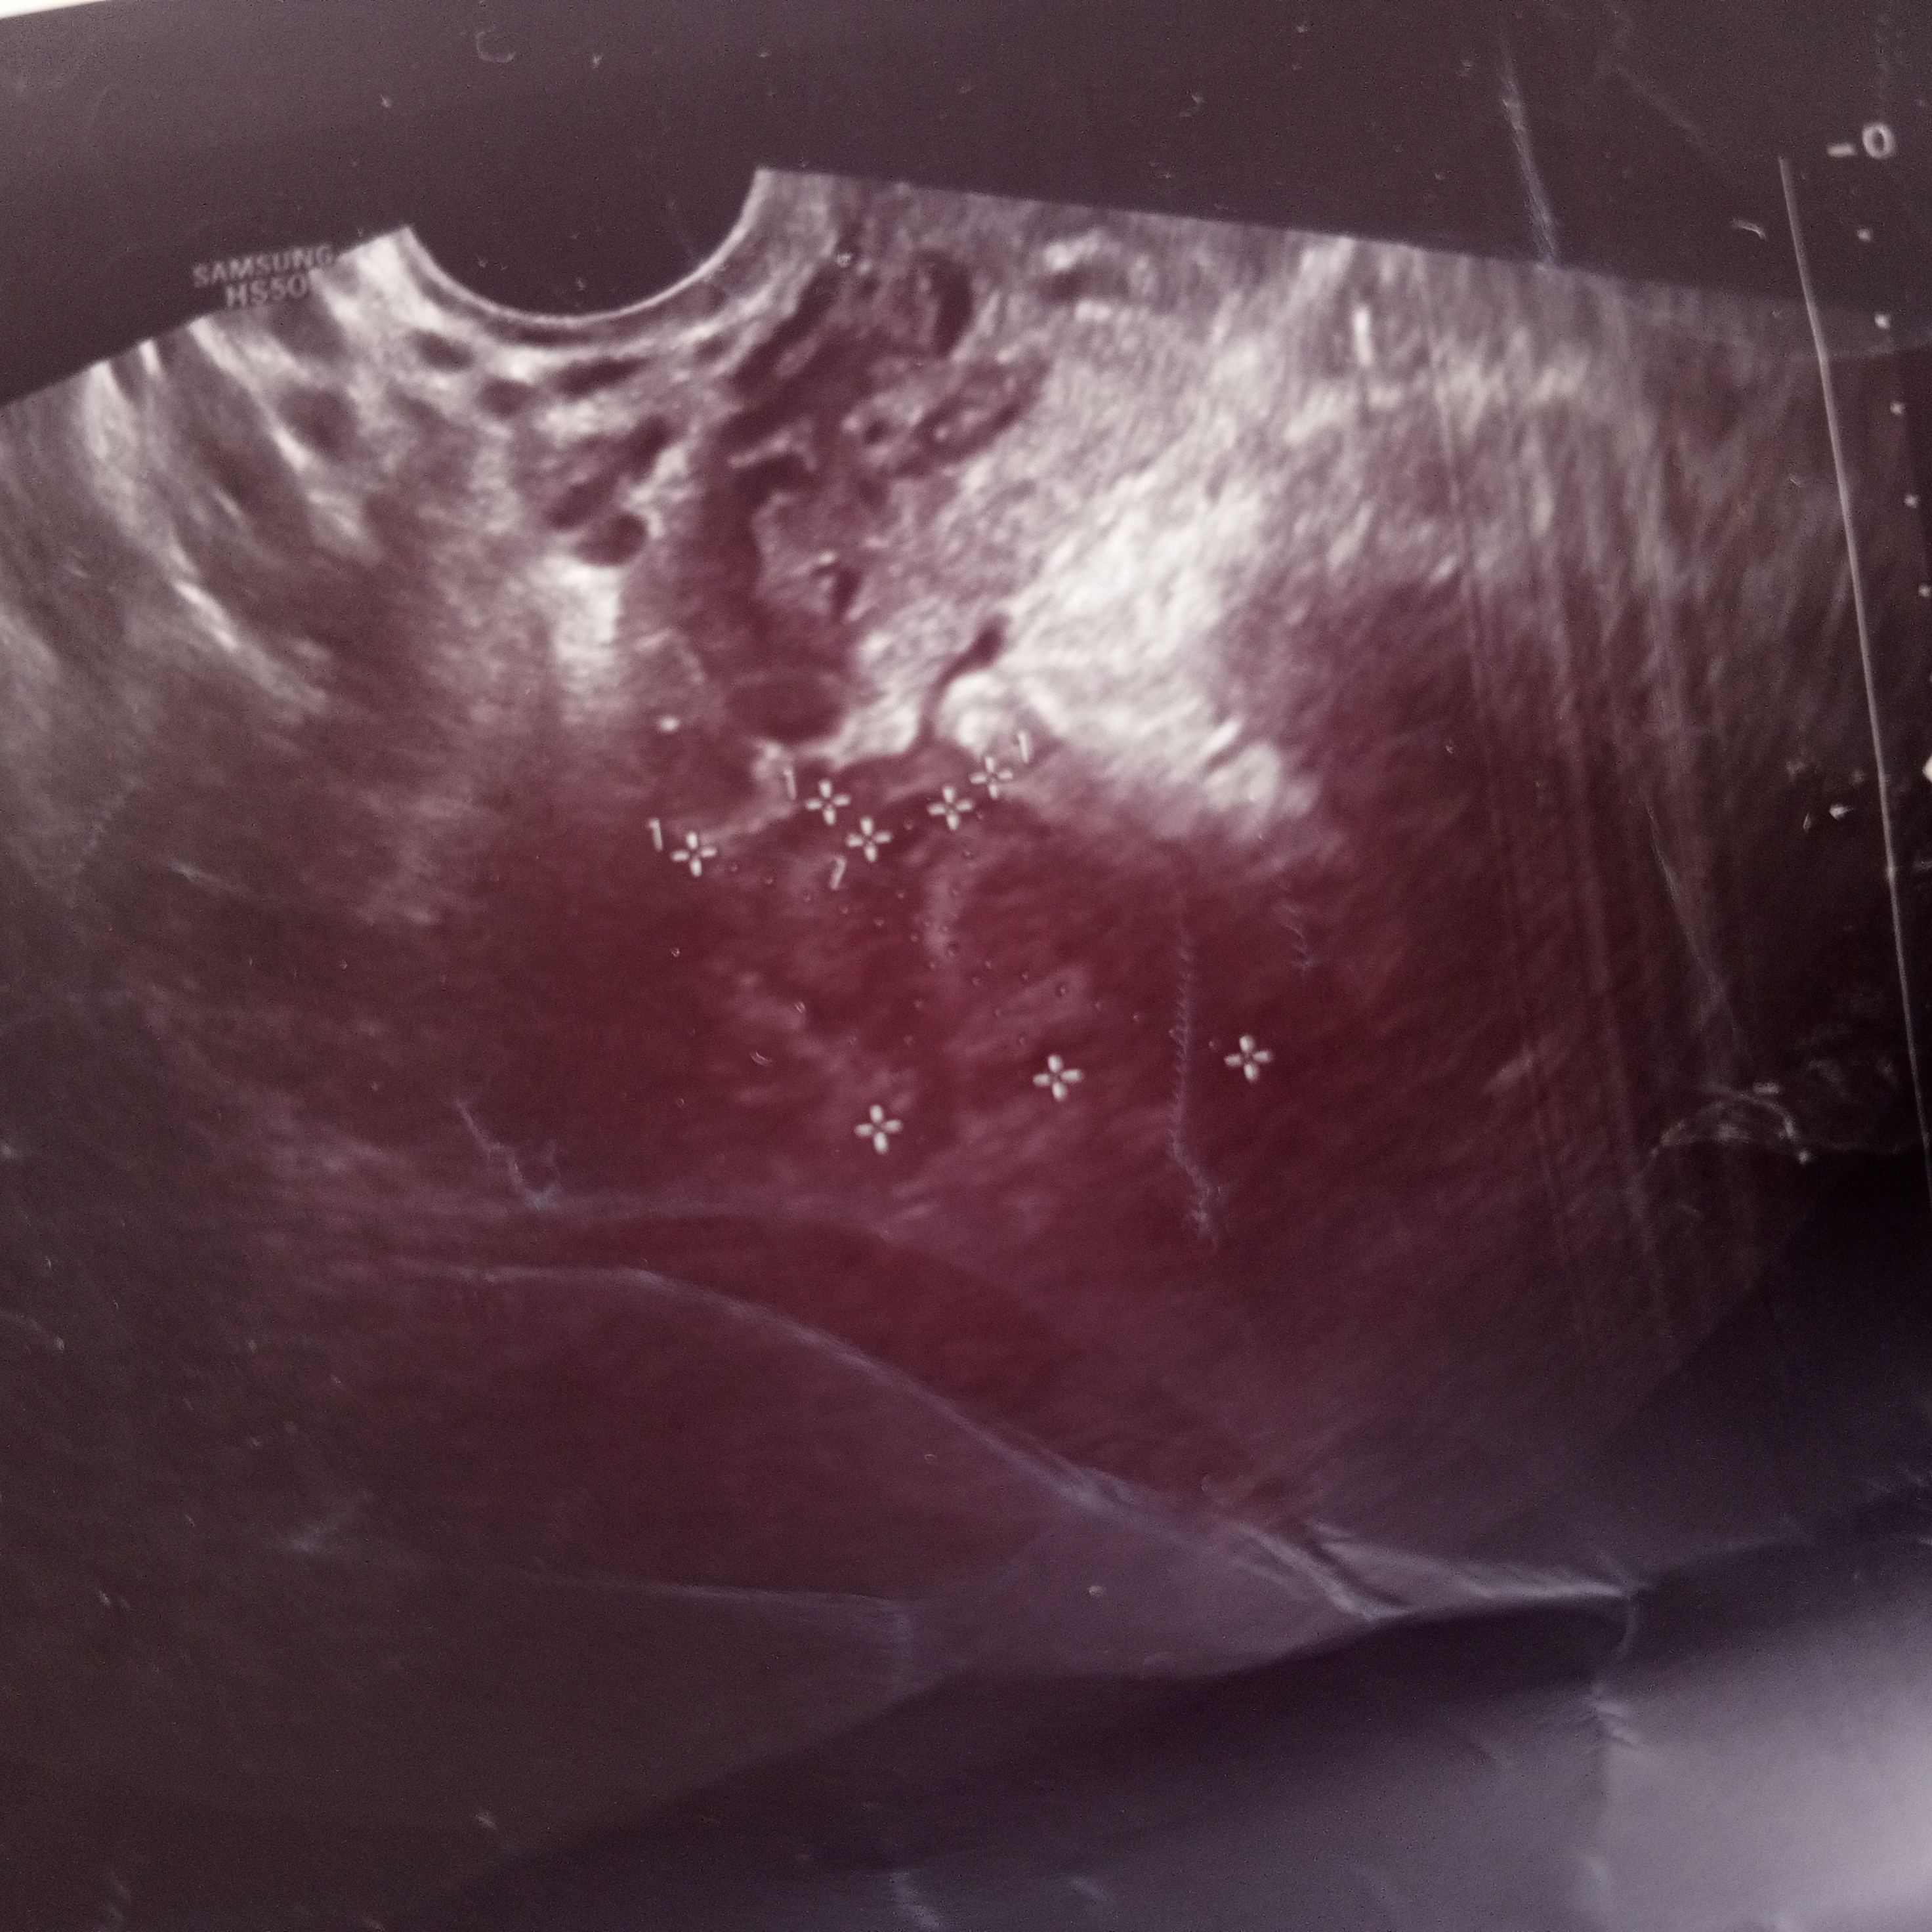

Девочки, сегодня на контрольное узи поеду, жт в ля но в правом посмотрите, я отметила, это не может быть жт? На 1 фоте обвела, второе оригинальное На фолликул не похоже так как он на узи черный а это как то выделяется